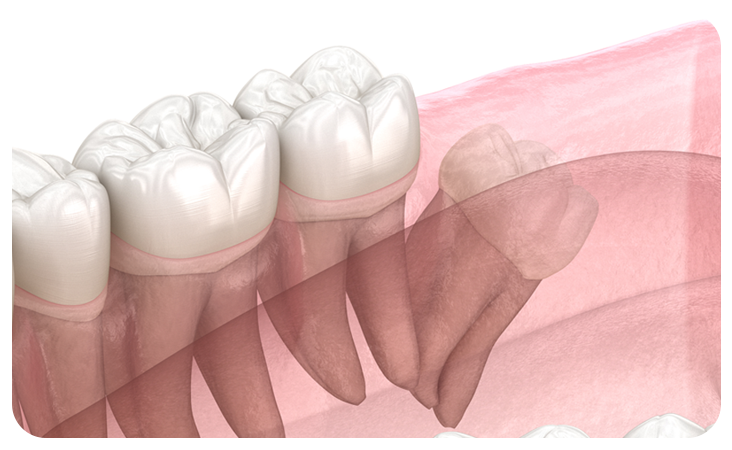

매복사랑니란?

사랑니가 완전히 맹출 되지 않고 잇몸 아래 묻혀있는

형태의 사랑니를  매복 사랑니라고 합니다.

사랑니가 완전히 맹출 되지 않고 잇몸 아래에 묻혀있는 형태의 사랑니를 매복 사랑니라고 합니다.

매복 사랑니는 함치성낭종, 염증 유발, 턱뼈 손상 등의 문제를 유발할 수 있어 발치해주는 것이 좋습니다.

부분매복

수직매복

원심경사 매복

수평매복